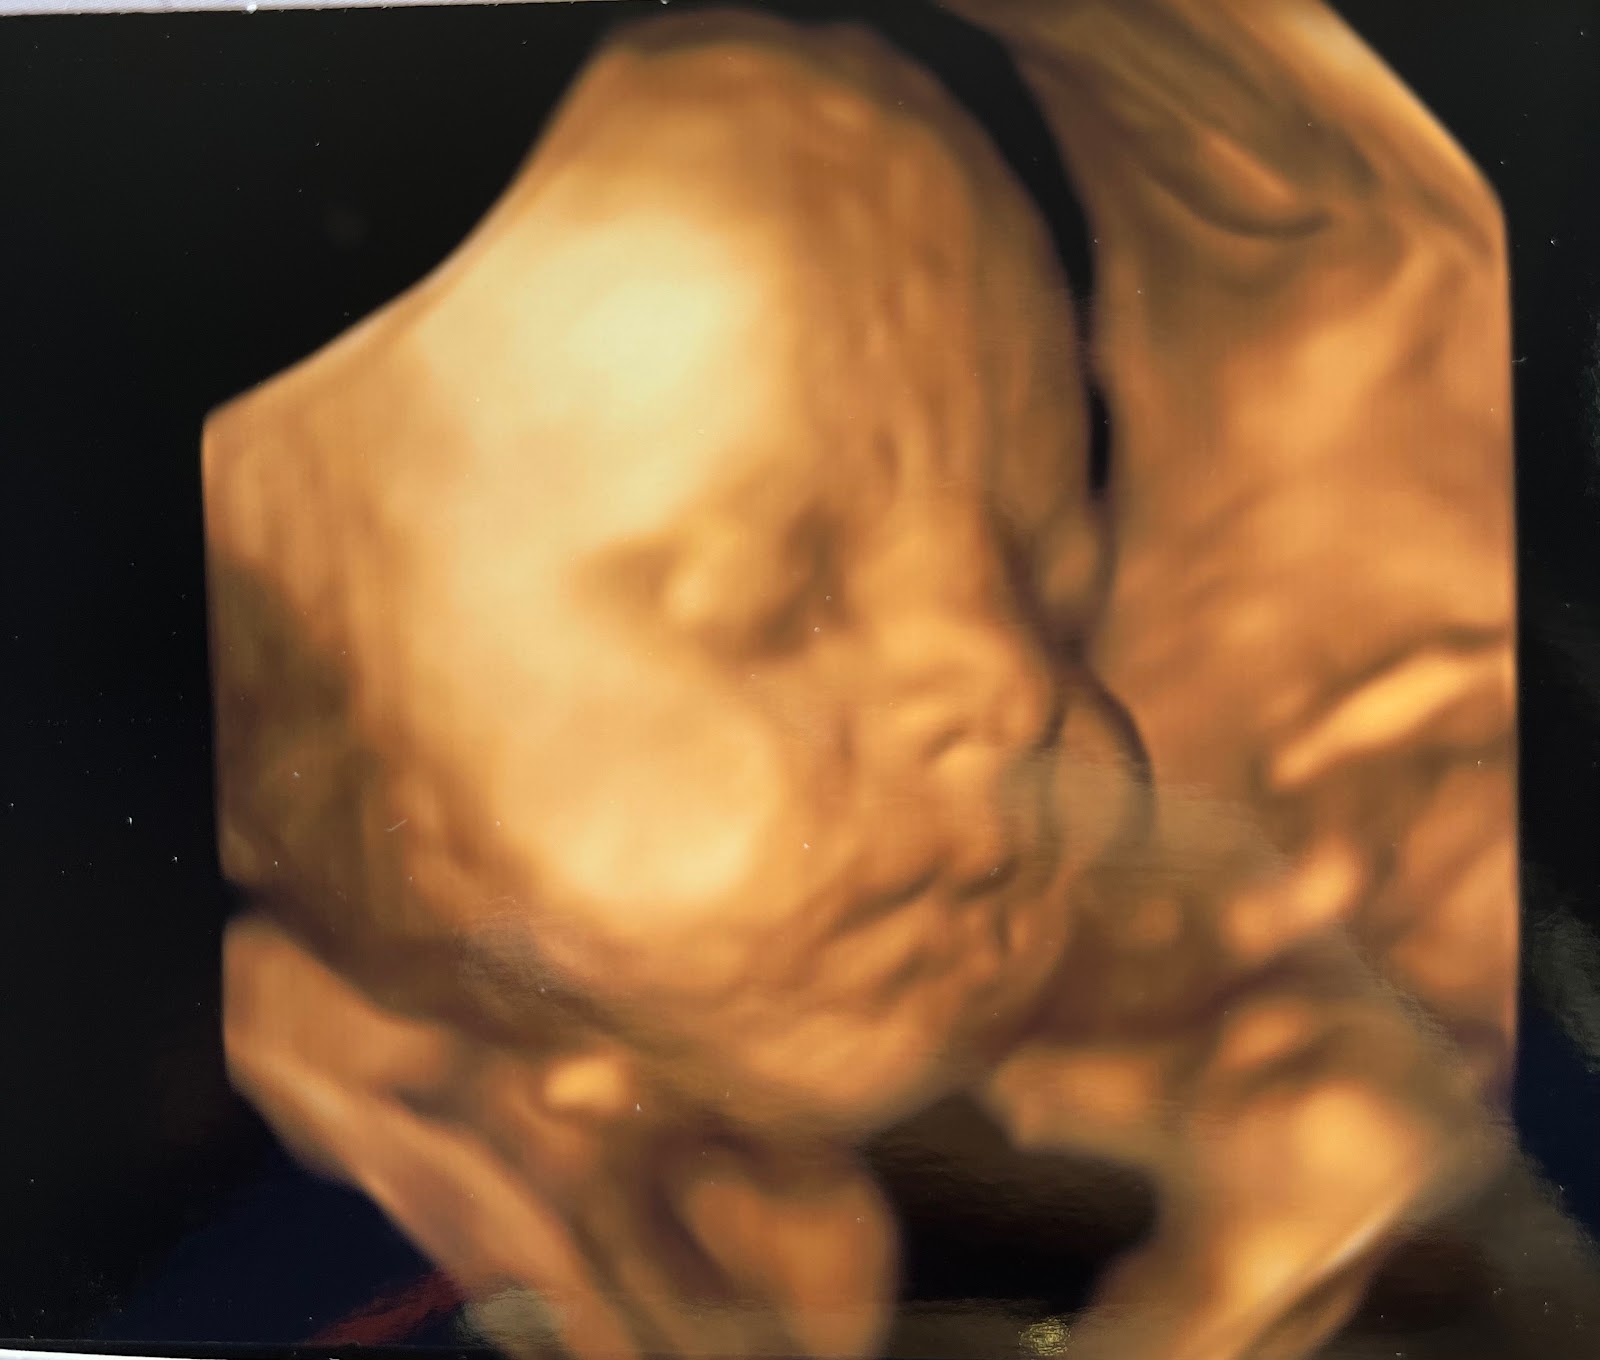

Közben pedig a Kisfiam folyamatosan növekszik, fejlődik a szívem alatt, lassan már meg is érkezik hozzánk, már csak pár hetet kell várni Rá. Folyamatosan mocorog, tudom, érzem, látom a jelenlétét, és ezzel megvalósult a legnagyobb álmom is.

Ő az én édes Babám (aki a képen nagyon békésnek tűnik, de valójában egész nap pörög, mint a motolla…😅), a 30. heti ultrahangon kb. másfél hete.